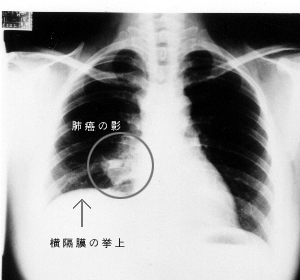

c、肺不張:腫瘤增大,加上炎性分泌物和水腫所致支氣管完全阻塞的結果。肺不張的直接徵象為:葉間裂移位,阻塞的肺葉、肺段密度增高,血管和支氣管影聚攏。間接徵象有縱隔和肺門向患側牽拉移位,膈肌升高,肋間隙狹窄,胸廓變狹。如肺不張伴有肺門腫塊時,可見肺不張下緣伸橫“S”形邊緣。

②周圍型肺癌:表現為密度不勻之不規則浸潤樣影,瘤體可呈平滑邊緣的無分葉球形,但多數情況下,瘤體邊緣是分葉狀的,即謂之“分葉征”。肺癌的分葉徵象出現率較高達80%,故對其鑑別診斷有一定意義。瘤體陰影的邊緣在X 線片上常較模糊而不銳利,典型者為細短狀毛刺影。如發生癌性空洞,形態可分為厚壁空洞、薄壁空洞和多發小空洞。空洞壁的各部分厚薄不勻,內壁不整,有時可見附壁結節。空洞多見於鱗癌。